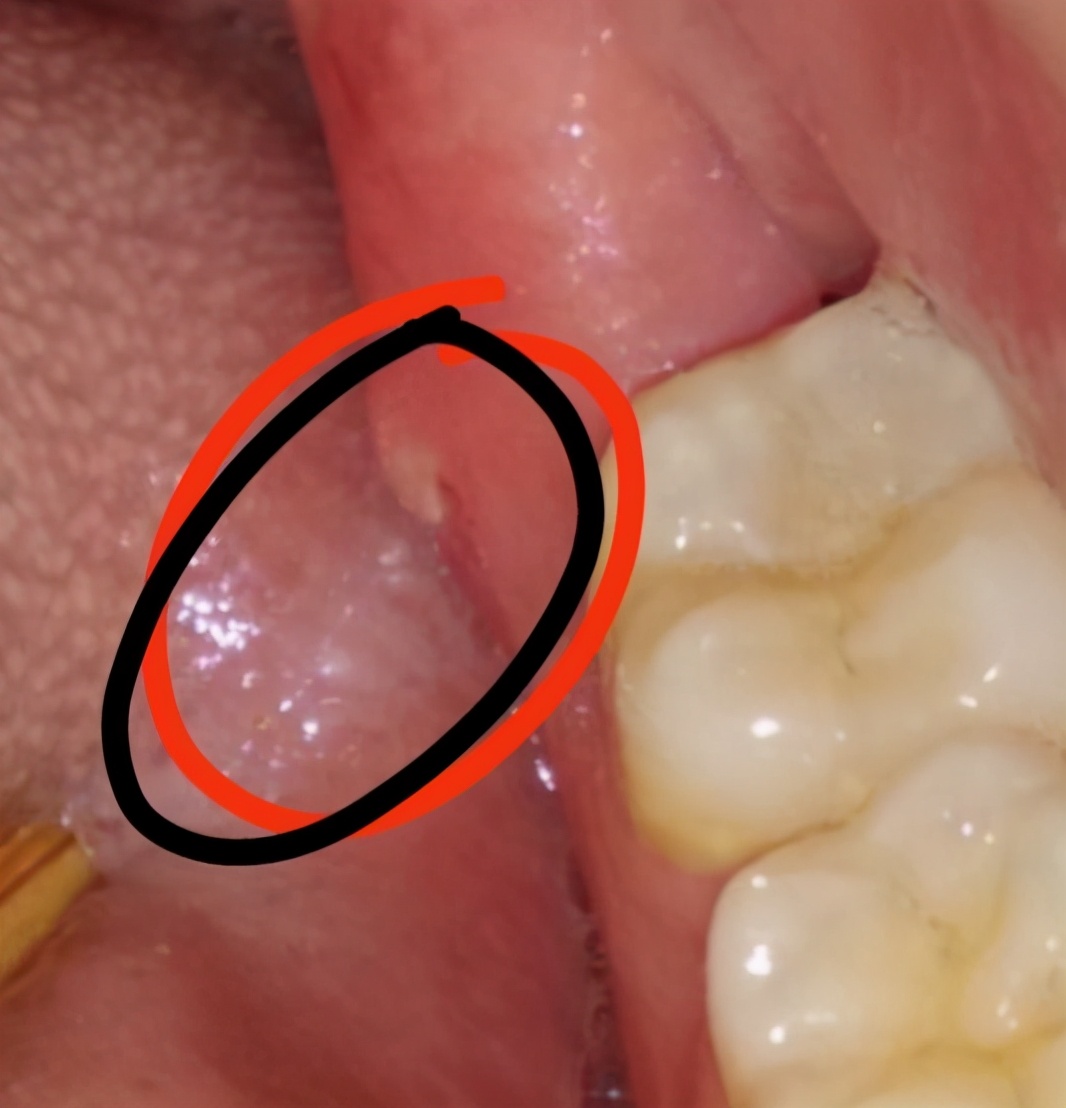

6、智齿生长期间,可能会在智齿周围冒出小骨刺,我们可以在每天刷牙后用手按摩骨刺部位,促进骨刺吸收和消除,亲测有效!